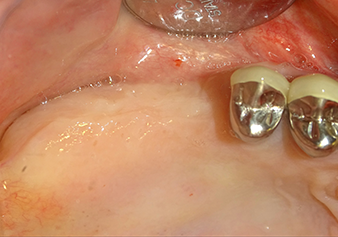

Dopo un controllo intermedio (Fig. 4) è stata eseguita un'ulteriore fase di preparazione (Fig. 5). Lo strumento idraulico Z35P è stato utilizzato in un secondo momento per sollevare la membrana sino alla posizione desiderata (Fig. 6 e 7). In seguito alla suddetta operazione, si è proceduto ad una ulteriore preparazione piezochirurgica della sede dell'impianto conclusasi con l'applicazione della fresa e della fresa a spallamento sul diametro dell'impianto di 4,8 mm. Il materiale di rinforzo (dimensione delle particelle di ca. 0,8 - 1,6 mm) è stato introdotto sotto la membrana di Schneider prima che venisse inserito l'impianto (Fig. 8).